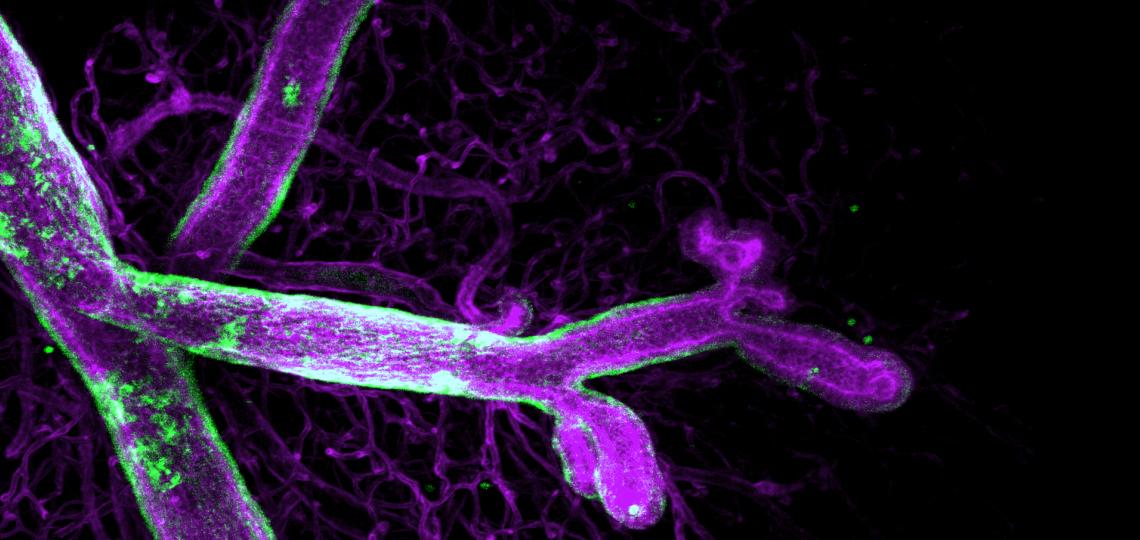

Human breast cancer organoid in a collagen-based 3D matrix

The cancer cells (magenta) lack the noncanonical Wnt receptor, Ror2. The protein fibronectin (orange) is up-regulated and assembled by Ror2-deficient tumor cells, triggering the invasion, dissemination and survival of cancer cells during metastatic transit. Nuclei are depicted in gray. The image was captured on the lab's Zeiss LSM 880 with Airyscan FAST Confocal Microscope.